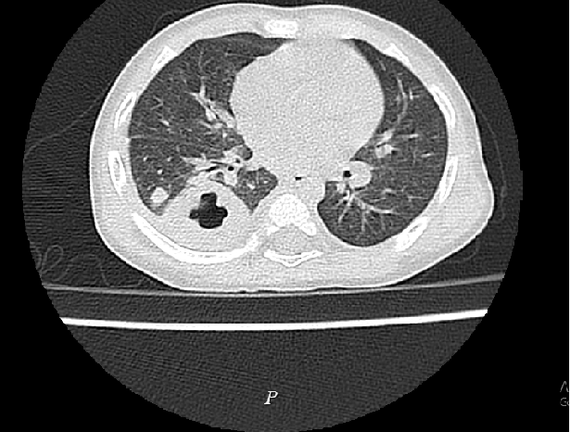

Nhận thấy đây là ca bệnh nặng, các bác sĩ cho bệnh nhi làm các xét nghiệm máu, chụp X-quang tim phổi, cấy máu, chụp cắt lớp vi tính phổi.

Kết quả chẩn đoán bệnh nhi bị nhiễm khuẩn huyết, áp xe phổi, được chỉ định điều trị kháng sinh liều cao phổ rộng.

Ảnh X-quang tình trạng nhiễm khuẩn huyết, áp xe phổi do vi khuẩn Withmore. (Ảnh: BVCC)